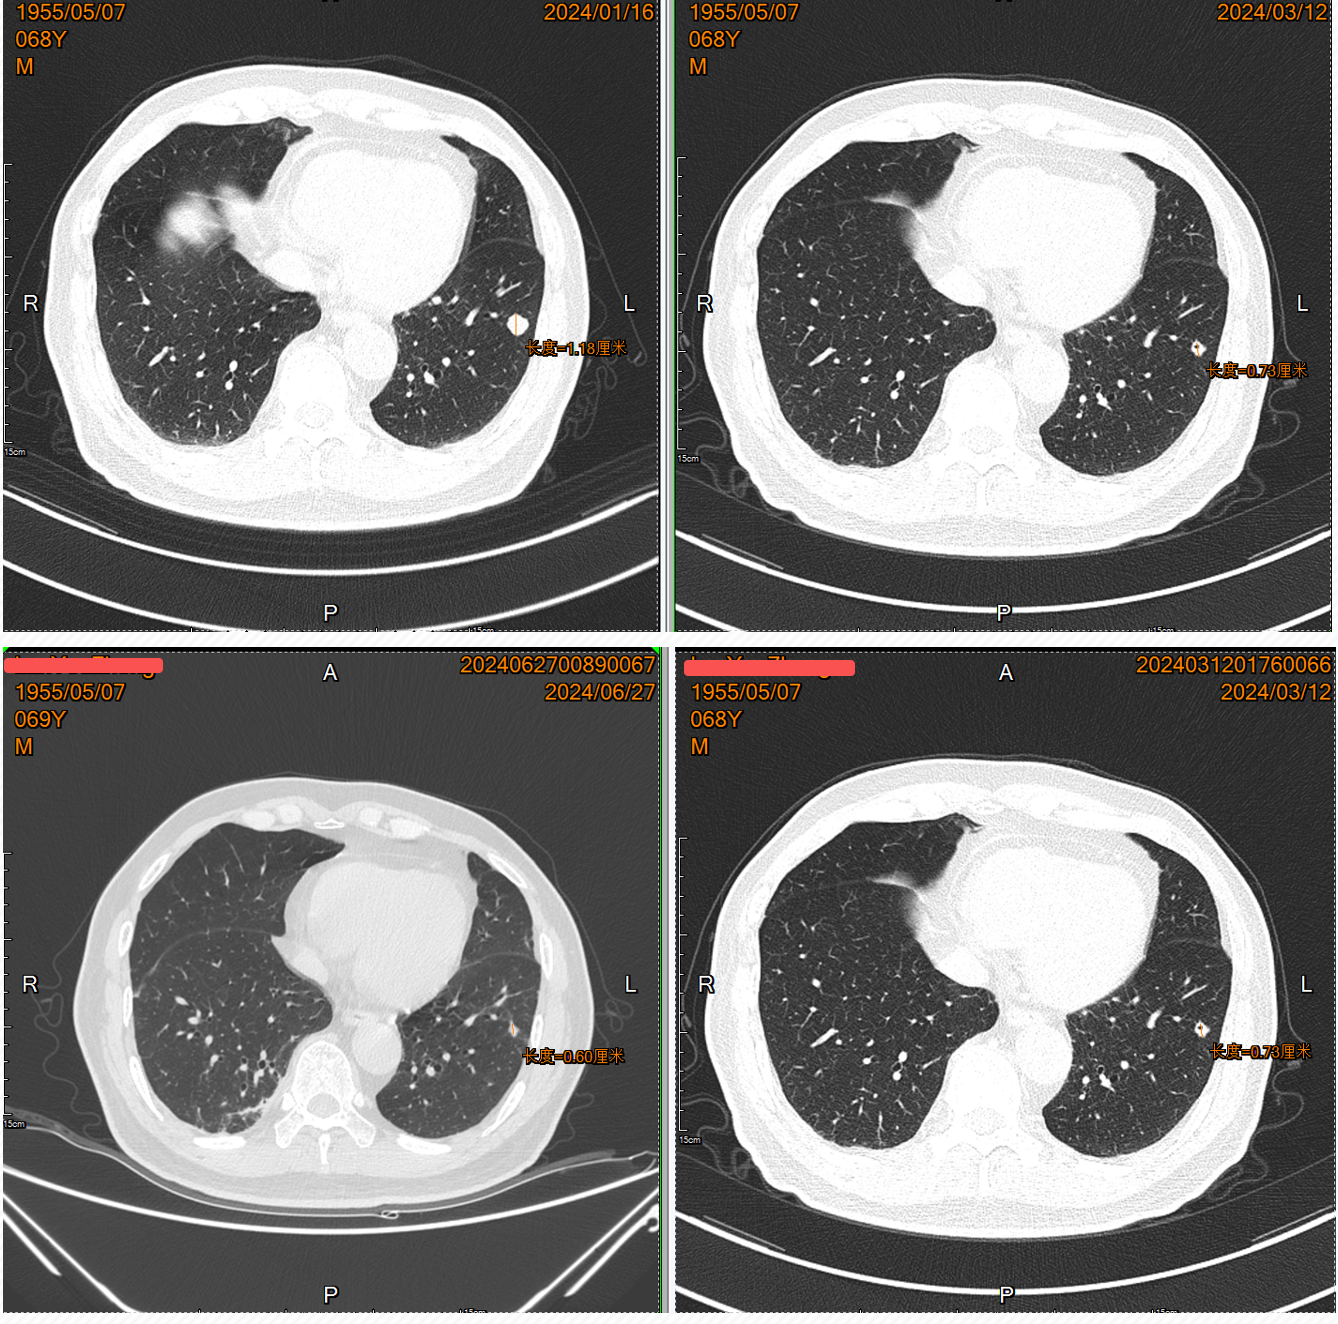

• 2024.01复查肺CT:双肺肺内可见多处小结节影,大者直径约为11mm,考虑转移瘤可能。余脑/骨/全腹盆腔未见明确复发转移

• 确诊右肾透明细胞癌并双肺多发转移(T2aN0M1 IV期)。IMDC及MSKCC预后评分:2分(初始至开始系统性治疗时间<1年/贫血)、中危。

• 2024.01予以“培唑帕尼200mg qd”靶向治疗;2024.03加量至“培唑帕尼400mg qd”靶向治疗

• 2024.3、2024.6复查:双肺肺内可见多处小结节影,部分缩小,部分结节内空洞形成。